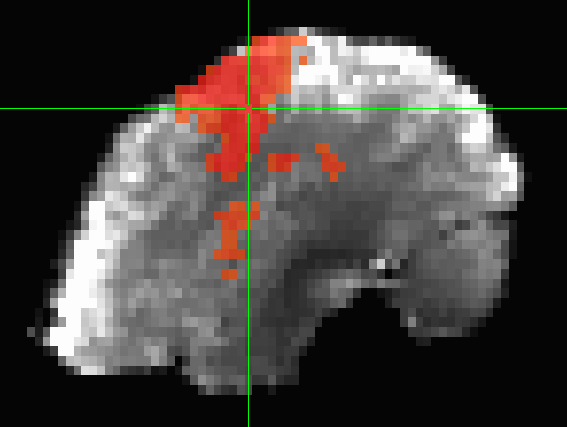

BOLD signal: "Functional Networks"

Biswal et al., 1995 (Magn. Reson. Med.)

Pearson correlation:

Whole brain functional connectivity

Huang et al., 2018 (Proc. IEEE)